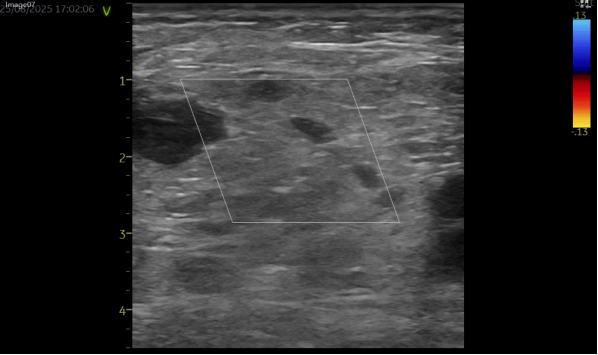

床旁超声检查提示:腹股沟区皮下可见特定范围的无回声区,边界清楚、形态欠规则,可见通道与动脉相连,动脉持续血流灌注;CDFI 示动脉与包块间分流口内可探及双向血流,包块内血流紊乱呈涡流,结合临床症状及检查结果,考虑为假性动脉瘤。

超声引导下凝血酶封堵术已成为临床处理假性动脉瘤的常用微创方式之一。该患者的手术过程顺利,在注射凝血酶 1 分钟后,超声复查显示瘤腔内活动血流消失,瘤体已血栓化,动脉与假性动脉瘤的通道封闭,听诊杂音及体表震颤感均消失。术后患者不适症状得到缓解,恢复顺利,次日出院(此为该患者个体恢复情况,不同患者因病情严重程度、体质、合并基础疾病等差异,恢复周期及效果可能不同)。